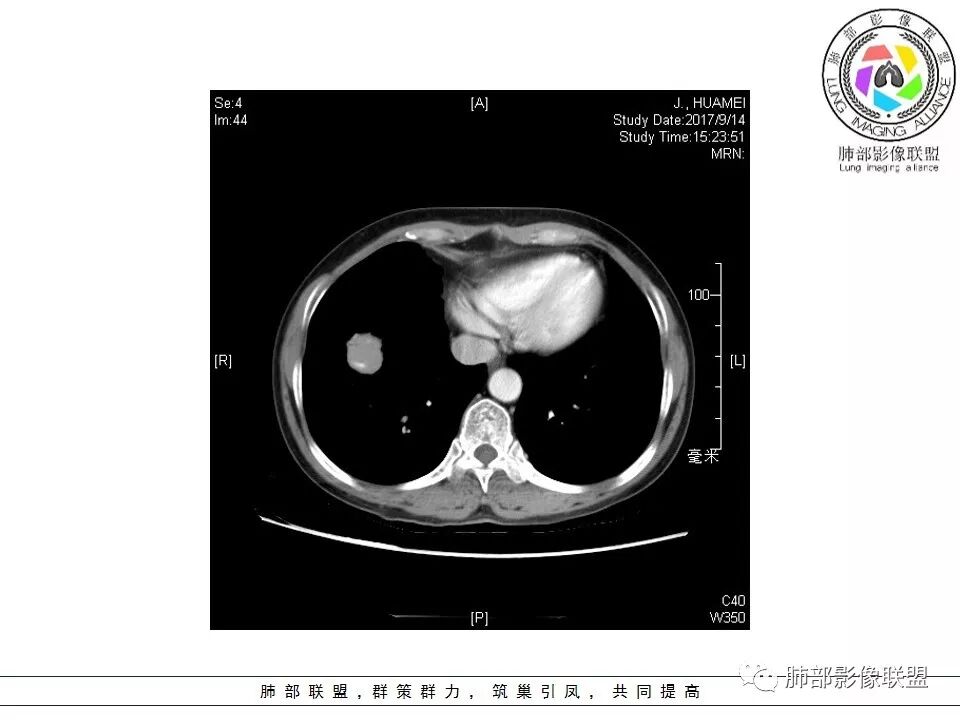

患者中年女性,因“体检发现右下肺占位4天。”入院,肿瘤标记物NSE轻高。

胸CT:右肺下叶前基底段占位性病变,内可见支气管穿过,病灶边缘不规则,呈浅分叶,未见明显毛刺。纵隔窗可见病灶密度相对均匀,增强可见病灶强化,内可见血管增粗,边缘模糊,总体考虑恶性,腺?。良性疾病鉴别错构。

这个病灶边缘还是有一点点恶性征象,有分叶,似乎有点地方还有一些小毛刺样感觉

部分区域整体以膨隆为主,部分区域稍收缩

内部支气管走形非常自然,达远端稍扩张;内部血管穿行也非常自然

内部密度比较均匀,我们一般来说,首先良性肿瘤不支持,因为它里面的血管走形太自然了;然后就是炎性病变跟恶性肿瘤,但是它的边缘膨隆比较厉害,有些地方还毛刺,不是很清楚,倾向一个恶性病变

恶性的血管穿行自然,包括支气管稍扩张,最常见还是淋巴瘤,它强化比较均匀;

粘液腺癌一般支气管扩张比较罕见,这个密度及强化太均匀,不是很符合,所以把淋巴瘤放前面,癌待排;

方向定在恶性的,炎性病变不是很符合